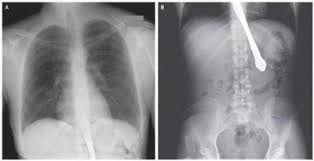

Pasien wanita itu mengatakan jika dia menelan sendok yang ia gunakan saat makan karena terburu buru saat memakan. Setelah diperiksa, kondisi wanita ini lebih serius dari yang diperkirakan. Dari pemeriksaan sinar X terlihat sendok berada dalam tubuhnya.

Sendok ini terletak di dalam perutnya dan bisa jatuh kedalam usunya kapan saja. Jika hal itu terjadi, sendok dapat melukai perut dan menyebabkan luka di dalam. Dalam beberapa kejadian, hal ini bisa mengakibatkan kematian.

Bentuk sendok yang bulat dan perutnya yang berisi makanan, membuat dokter kesulitan mengeluarkannya. Membutuhkan waktu 2 jam hingga akhirnya para dokter berhasil mengeluarkan sendok tersebut.